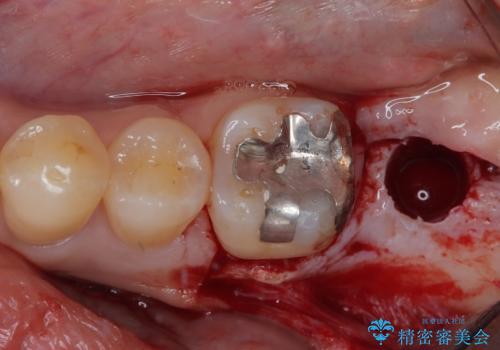

上顎の奥歯は、左右ともに外側に転位しており、特に右上はむし歯の範囲が広く、根管治療も必要な状態でした。

左下の奥歯は状態が非常に悪く、保存は困難と判断されたため、インプラントによる補綴治療が必要でした。

上顎左右の歯をアンカースクリューを用いた部分矯正により位置を修正し、オールセラミッククラウンにて補綴治療を行うこととしました。